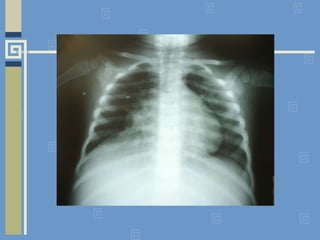

RX: A imagem é “pneumonia”?

RX: A imagemé “pneumonia”?